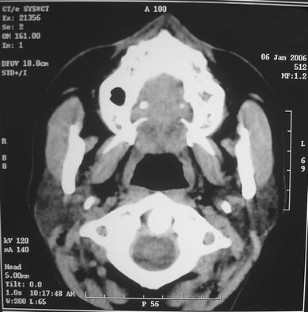

Fig. 1